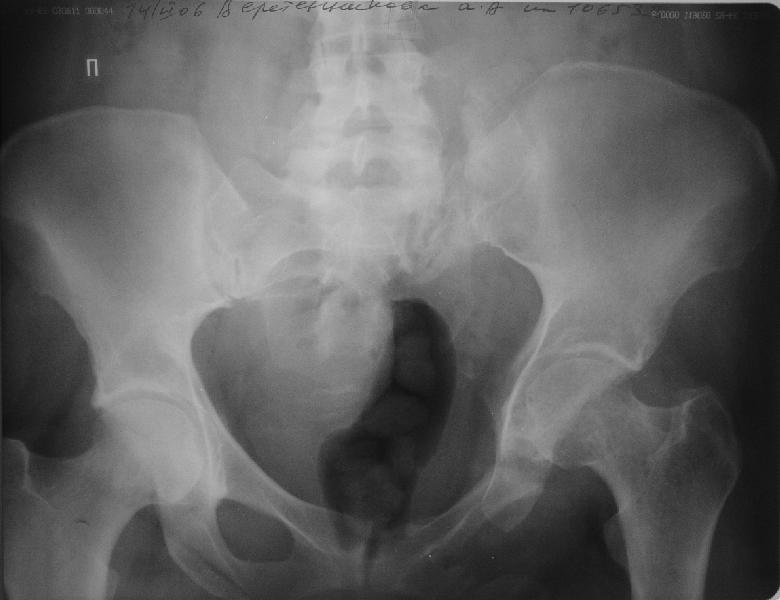

Прооперировали молодую девушку 32 лет спустя 9 мес после травмы. Имелся стойкий болевой синдром, неопороспособность левой н/конечности, моторные и сенсорные нарушения в левой голени и стопе, патологическая подвижность левой половины таза. Первым этапом закрыто в аппарате исправили деформацию ( в течении 2,5 нед). Вторым закрытое введение илиосакральных винтов в крестец (канюллированные 7,2 мм Chm) + туннелизация зоны псевдоартроза спицама Киршнера, реконструкция передних отделов таза, накостный остеосинтез . Аппарат частично демонтирпован, оставлена "передняя рама" После устранения деформации отмечен регресс неврологической симптоматики, уменьшение болевого синдрома. Интересующие вопросы: 1. Прогноз для сращения псевдоартроза крестца. 2. сроки нагрузки весом левой половины таза. Буду очень признателен за ваши мнения по этому поводу.A female 32 y.o. admitted to our unit 9 months after initial injury with pain, inability to bear weight at the left lower limb, sensor and motor disturbances in the left foot and tibia, with mobility of the left hemipelvis.At first closed reduction was performed by an external fixator within 2,5 weeks. After correction her pain decreased and some neurological progress was achieved. Now two iliosacral screws 7,2 mm were inserted, and anterior lesion was fixed by a plate. External fixator was partially unmounted, only anterior frame left in place.Images attached.How would you evaluate chances of healing of the sacrum with the current position?When would you allow weight-bearing of the left leg?THX in advance.